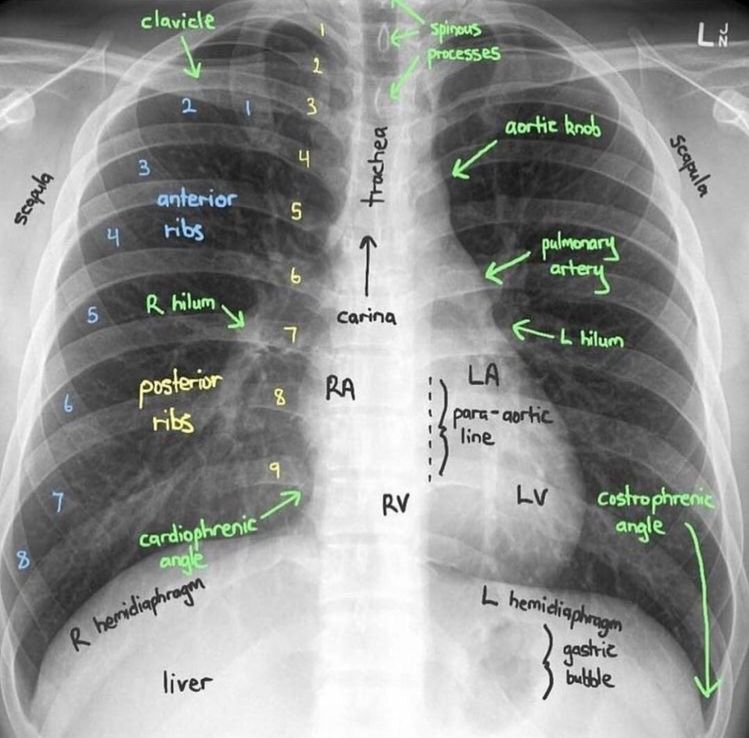

This CXR shows what normal demarcations look like in a chest x-ray of healthy individual.

Very informative, rib counting looks easier now